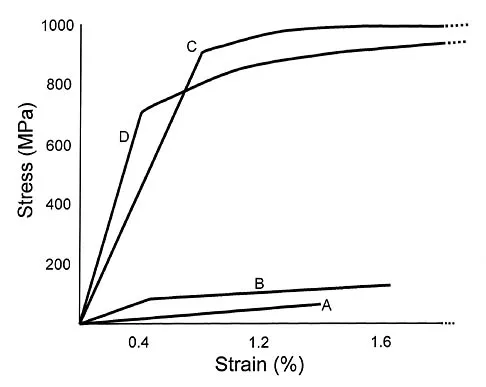

What is the most common cause of mechanical failure of an orthopaedic biomaterial during clinical use?

Explanation